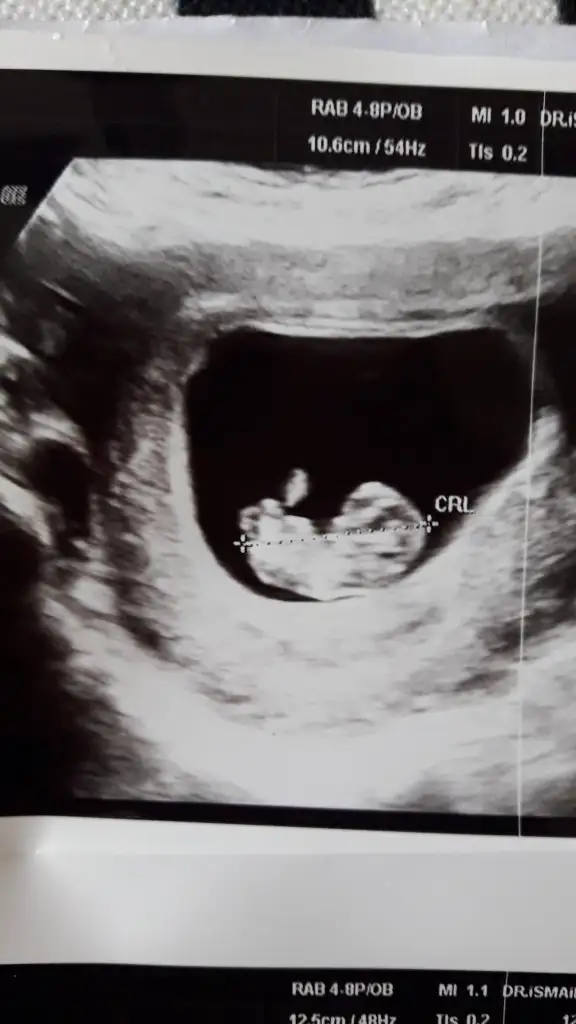

Kız gibi tam net degil 12 hafta usg de paylaşın bir dakineİyi pazarlarbende bir tahmin alabilir miyim acaba ? 10 hafta 5 günlük usg görüntüsü eklediğim.

Kiz gibi net degilİyi pazarlarbende bir tahmin alabilir miyim acaba ? 10 hafta 5 günlük usg görüntüsü eklediğim.